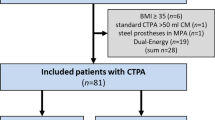

From July 2015 to March 2017, 20 patients with stage I lung tumours or lung metastases referred for stereotactic ablative radiotherapy (SABR) were prospectively included in this study (Table 1). Patients able to understand the instructions related to CPAP and with tumours expected to move significantly (apical tumours excluded) were eligible. One of the patients had two treatments 1 year apart and was recruited twice (#6 and #14). A total of 24 tumours were treated. Histological confirmation was available in 13 patients, who all had primary lung tumours. In other patients, malignancy of the pulmonary nodule was suspected based on imaging features, e.g. morphologic characteristics of malignancy, growth on consecutive CT scans and/or hypermetabolism on positron emission tomography (PET)/CT.

CPAP increased lung volume by 296 mL (SEM: 73; p < 0.001) and 243 mL (SEM: 52; p < 0.001), which corresponds to a mean relative increase of 8.0% (SEM: 2.2) and 6.3% (SEM: 1.3) at T0 and T1 time-points, respectively. The change in lung volume induced by CPAP showed a wide inter-patient variability (Fig. 1 and Table 2). For example, while some of the patients showed a large increase in lung volume at T0 (#16, #18 and #19; Fig. 2), two of the patients (#10 and #13) displayed a slight decrease, for which there is no obvious physiological explanation apart from anxiety (patient #13 was the one who did not tolerate CPAP well). Overall, the change in lung volume induced by CPAP at T0 was similar to T1 (interaction F = 0.31, p = 0.56). However, the intra-patient reproducibility was relatively low (Fig. 1).